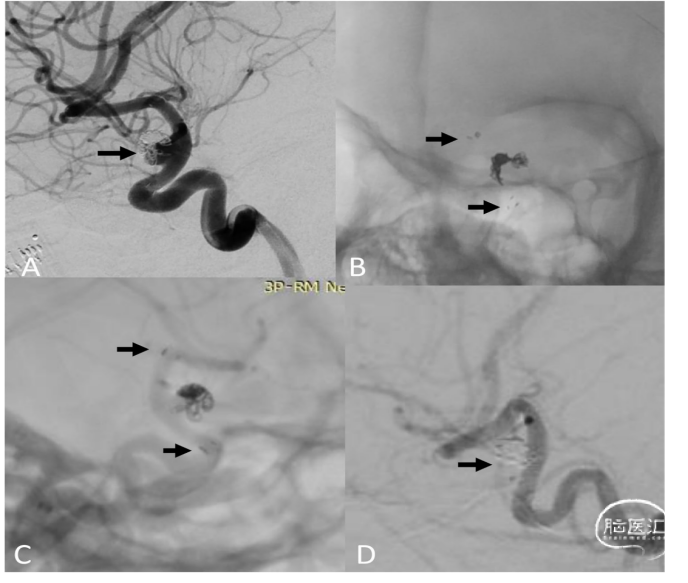

图3:一名66岁男性患者因椎动脉瘤破裂接受了LVIS支架辅助弹簧圈栓塞术,术后6个月复查。

A. 数字减影血管造影,斜位视图,显示动脉瘤残留(白色箭头)以及LVIS支架近端动脉狭窄(黑色箭头)。为改善载瘤动脉近端狭窄,进行了球囊血管成形术,并植入一枚Pipeline栓塞装置以覆盖3个动脉瘤。

B. 未减影图像显示先前植入的LVIS支架、弹簧圈以及Pipeline栓塞装置在支架内完全展开(箭头所示)。

C. 6个月随访时的减影血管造影图像显示动脉瘤完全闭塞,动脉狭窄得到改善